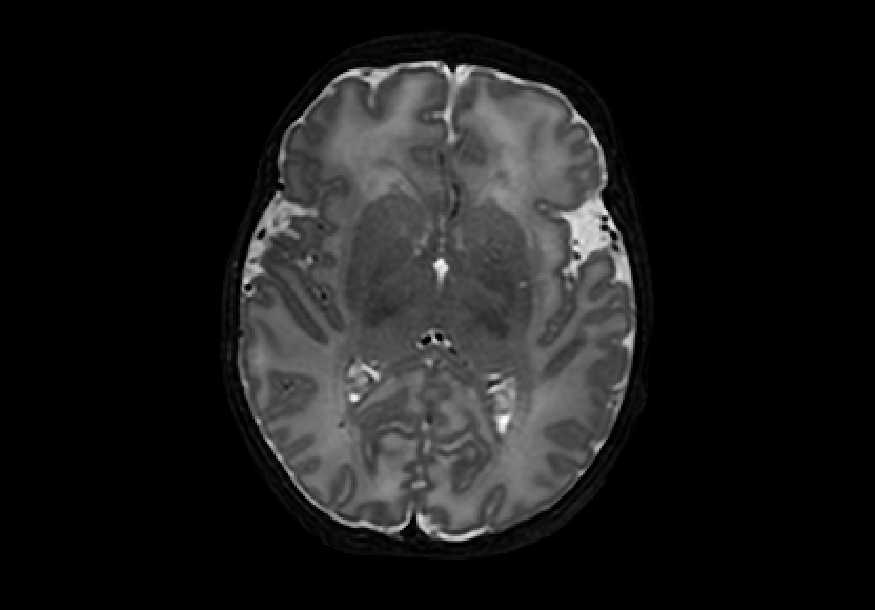

The dataset consisted of 70 3D T2-weighted brain MRI scans publicly available from the dHCP neonatal cohort. The segmentation maps had 10 classes, corresponding to: zero-pixel background, cerebrospinal fluid (CSF), cortical grey matter (cGM), white matter (WM), background bordering brain tissues, ventricles, cerebellum, deep grey matter (dGM), brainstem, and hippocampus. The scans covered an age range of 24.3-42.2 weeks. The data was available in NIfTI format; Figure 1 shows an example scan and corresponding tissue labels. We carried out a pre-processing step where each scan was independently normalised to zero-mean and unit-variance.